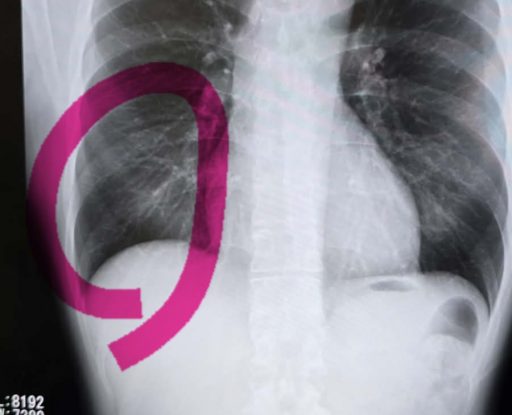

中澤さんが折れてる可能性があるから CT撮って院長に見てもらいなさいと

「日曜日のレントゲンを見ても 折れてなさそうだけどねぇ」と言うので

折れてるね!と笑っていた

院長先生 「あれ!折れてるわ!」と

救急の先生がどれだけ適当なのか・・・・・・